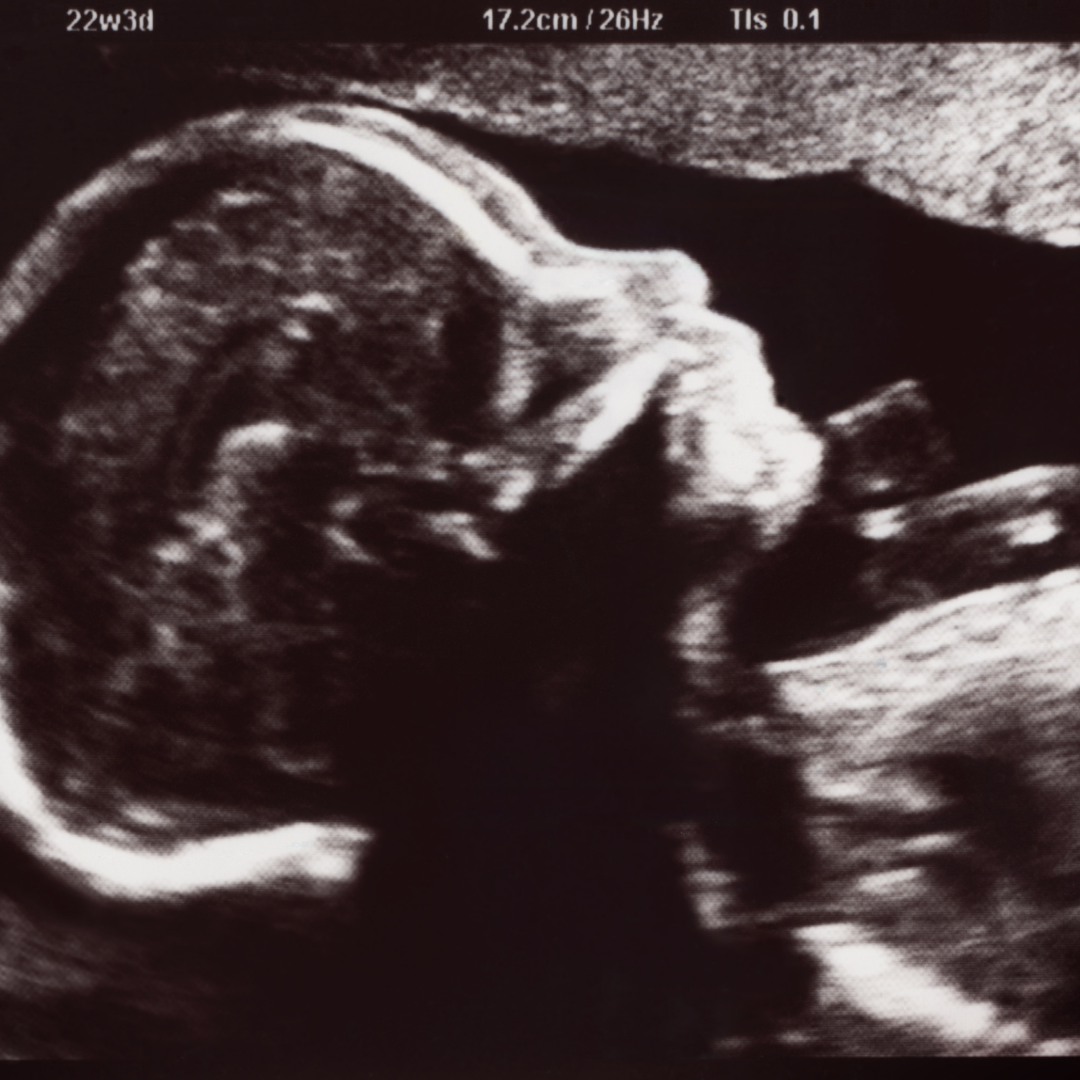

Sonografía Obstétrica

Permite monitorear el desarrollo del bebé, la placenta y el líquido amniótico durante el embarazo. Es una herramienta esencial para el seguimiento prenatal.

Sonografía Morfológica

Estudio detallado de la anatomía fetal realizado entre las semanas 18-24. Evalúa el desarrollo de órganos, extremidades y detecta posibles malformaciones estructurales.